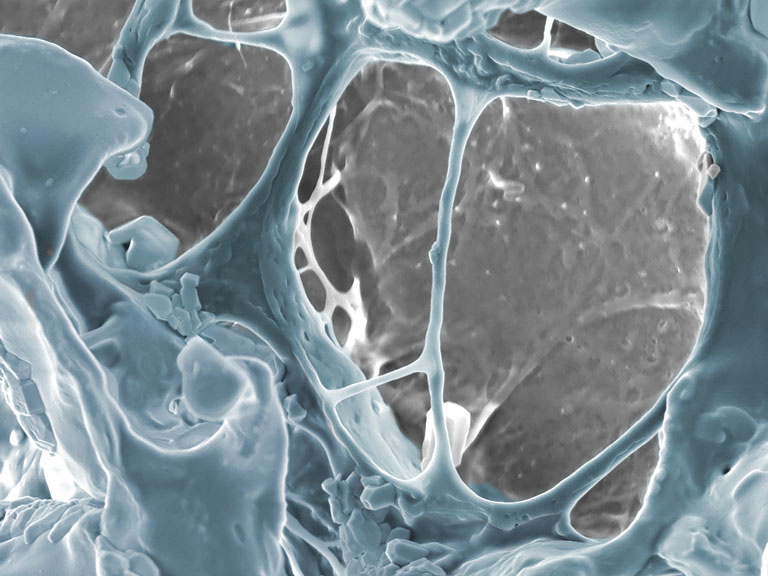

Autologous blood therapies, such as the delivery of platelets and platelet rich plasma, are of increasing interest for wound healing, but are short acting and currently require repeat clinic visits. Here, we aim to develop a microneedle patch for the sustained delivery of preserved autologous platelet-based therapies for the treatment of chronic wounds. Biocompatible and bioresorbable, these hydrogel microneedles can deliver platelet-based therapies for approximately one week and can retain their ECM-mimicking properties for longer as they biodegrade.